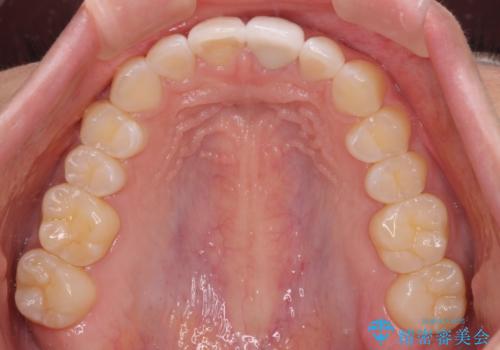

気になる前歯を治したい インビザライン矯正とオールセラミッククラウン

- 変色した前歯と突出した口元を気にして来院された患者様です。

口元の突出感はインビザラインにより歯列を整え、その後に、前歯をオーダーメイドタイプのオールセラミッククラウンにて補綴治療することとしました。

長時間のマウスピース装着と、患者様自身でのゴムかけに協力いただき、口元の突出感をしっかりと改善することができました。

前歯のオールセラミッククラウンもまるで本物の歯のように仕上がり、患者様には大変満足していただきました。